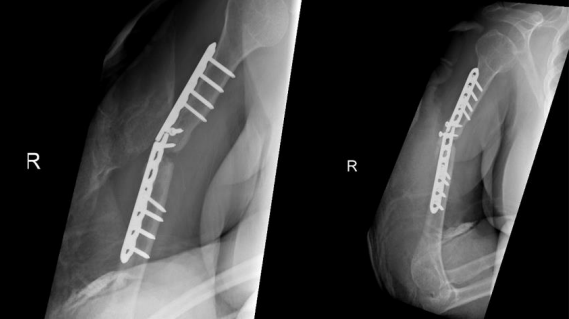

On serial follow-ups, the patient was asymptomatic clinically and had no evidence of healing on radiographs. Then, on 15 May 2019, around 9 months post first revision she reported persistent localized pain to the fracture site, and with radiographic evidence of complete resorption of the allograft and non healed fracture a nonunion diagnosis was established (Figure 3).

Figure 03

Options was discussed and The decision was made to take the patient for surgery for the third time “second revision” on17 June 2019. The sclerotic bone was excised, which accounted for 2.5 cm in length, and replaced with a tricortical iliac crest strut autograft, cancellous graft, and putty bone substitute. The same plate was applied, and new screws were used to hold the graft in place. The remaining screws were inserted, and the device was stable intraoperatively. Postoperative radiographs are shown in Figure 4.

Figure 4